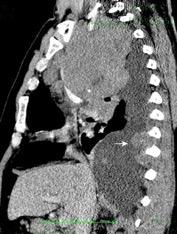

Marzo 2014: Perforación longitudinal distal secundaria a episodio de vómito (síndrome de Boerhaave). Derrame pleural izdo. que evoluciona a empiema.

Wang C-T et al. Tension hydropneumothorax in a Boerhaave syndrome patient: A case report . World J Emerg Med, 2021. Katabathina V et al. Nonvascular, nontraumatic mediastinal emergencies in adults:a comprehensive review of imaging findings. Radiographics. 2011.